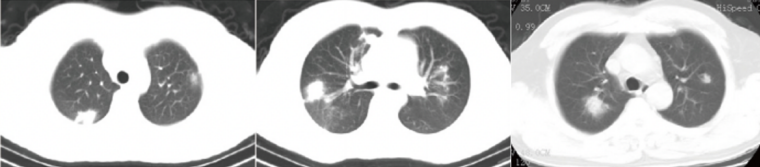

IPA的CT影像学有多种表现,从非特征性的气道病变逐渐演变为特征性的血管侵袭为主[4]。曲霉菌侵袭累及肺泡和细支气管壁,影像学可呈现非特征性改变如支气管周围实变影、支气管扩张征、小叶中心型微小结节影、树芽征和磨玻璃样改变等表现,为曲霉菌气道侵袭特征性表现。IPA特征性CT影像学包括:致密、边界清楚的病变(伴或不伴晕征)、空气新月征、空洞、楔形/节段性或大叶性病灶[1]

IPA患者可出现特征性或非特征性CT改变,且疾病不同阶段CT表现存在一定差异。IPA患者的CT表现与免疫缺陷类型或程度及潜在宿主疾病相关,严重免疫抑制时免疫反应极为有限;而免疫恢复/重建时,反应将增加、病变可能会扩大。边界清晰的病变(结节)是IPA的主要影像学表现;不同影像学表现可能代表疾病的不同阶段[5]。针对免疫缺陷患者,IPA的CT特征随疾病进展而有不同表现:疾病早期以晕轮征为主,随后以空气新月征、空洞常见[6];此外,患者初期病变数量及大小增加,随后进入减少的平稳阶段[7]

IPA患者还可表现为非特异性和不常见的CT改变,如实变、空洞性病变、胸腔积液、磨玻璃样混浊、树状浸润性病变和肺不张等,但非特异性CT可能会进展为特异性表现。IPA的特异性征象包括:小结节(<10 mm)、树芽征、磨玻璃病变、气腔实变等。病理基础为曲霉菌侵袭气道致气腔内渗出,影像上不具有特异性,细菌、病毒感染均可出现这些征象。真菌感染非特异性征象出现概率较小,其原因可能是机体免疫力提高或抗真菌治疗使病变很快被吸收或迅速进展为血管侵袭期,所以出现时间短。

IPA的特征性影像:①大结节:>10 mm,影像特点:一般双肺多发,形态不规则,边缘毛糙,可有分叶,倾向于中上肺野分布;病理基础:血管侵袭期形成炎性肉芽肿,中心凝固性坏死。②晕征:影像特点为结节周围见模糊淡薄磨玻璃渗出,边界不清。病理基础:病变侵袭血管致血管出血,渗出至结节周围形成“晕征”。渗出短时间内吸收,因此“晕征”出现的时间也较短。③空洞:影像特点为多态结节内出现空洞,部分空洞内见细网状分隔或结节(形成空气半月征)。病理基础:机体免疫力提高或抗真菌治疗有效,菌丝被切断,原本被菌丝抓住的凝固性坏死物质逐渐排出,当部分排出时,空洞内残留部分菌丝及坏死物质,即形成网状分隔;若空洞内残留菌丝及坏死物质形成结节,结节与空洞之间形成“空气半月征”;若坏死物质全部排出即形成空洞。

图片

结节

晕征

空洞